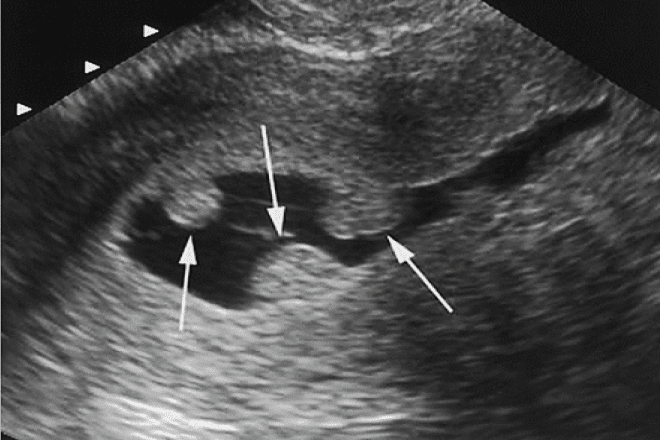

16

Q

Qual o diagnostico

A

Mioma